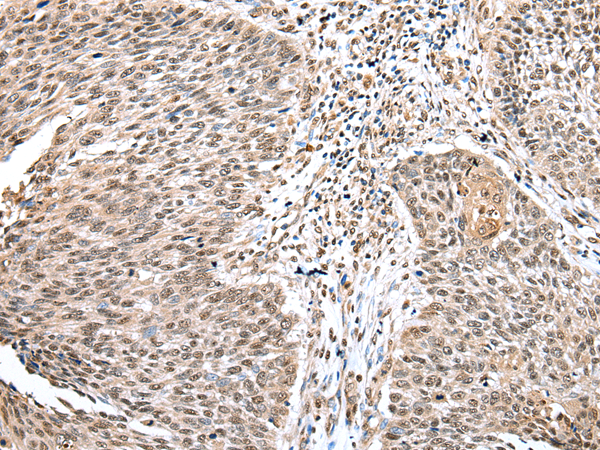

分类: 科研抗体货号: P02020别名: Ipi3; R32184_1应用: WB,IHC反应种属: Human, Mouse